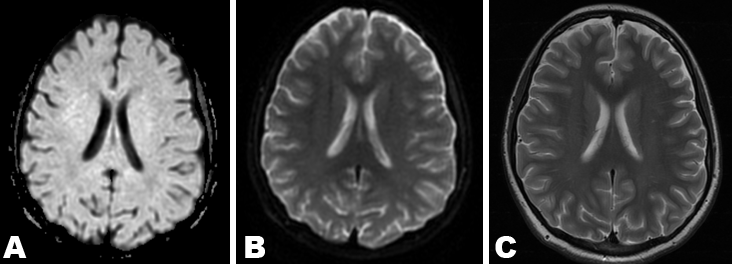

Despite anticonvulsive therapy our patient continued to have left-gaze preference and right hemiparesis, which persisted for three days. It also became evident that despite being intubated she appeared to have a receptive aphasia. Given the MRA showed what appeared to be vasospasm of the left MCA it was elected to give a trial of intravenous MgSO4. She received 3 g (15 mg/kg) of MgSO4 in divided doses with significant improvement of her symptoms within three hours and complete resolution of her gaze preference, aphasia and hemiparesis within 24 hours. Twelve weeks after discharge from the inpatient setting her neurological examination, including cognitive and motor functioning, were completely normal. Repeat MRI scan of brain six weeks after onset of symptoms revealed complete resolution of the signal abnormalities in the SCC on DWI, ADC and axial FLAIR sequences (Figure 3A–C).

Figure 3: Repeat magnetic resonance imaging scan of brain six weeks later demonstrating complete resolution of the splenial lesion on diffusion weighted imaging (A) Apparent diffusion coefficient (B) and T2 (C).